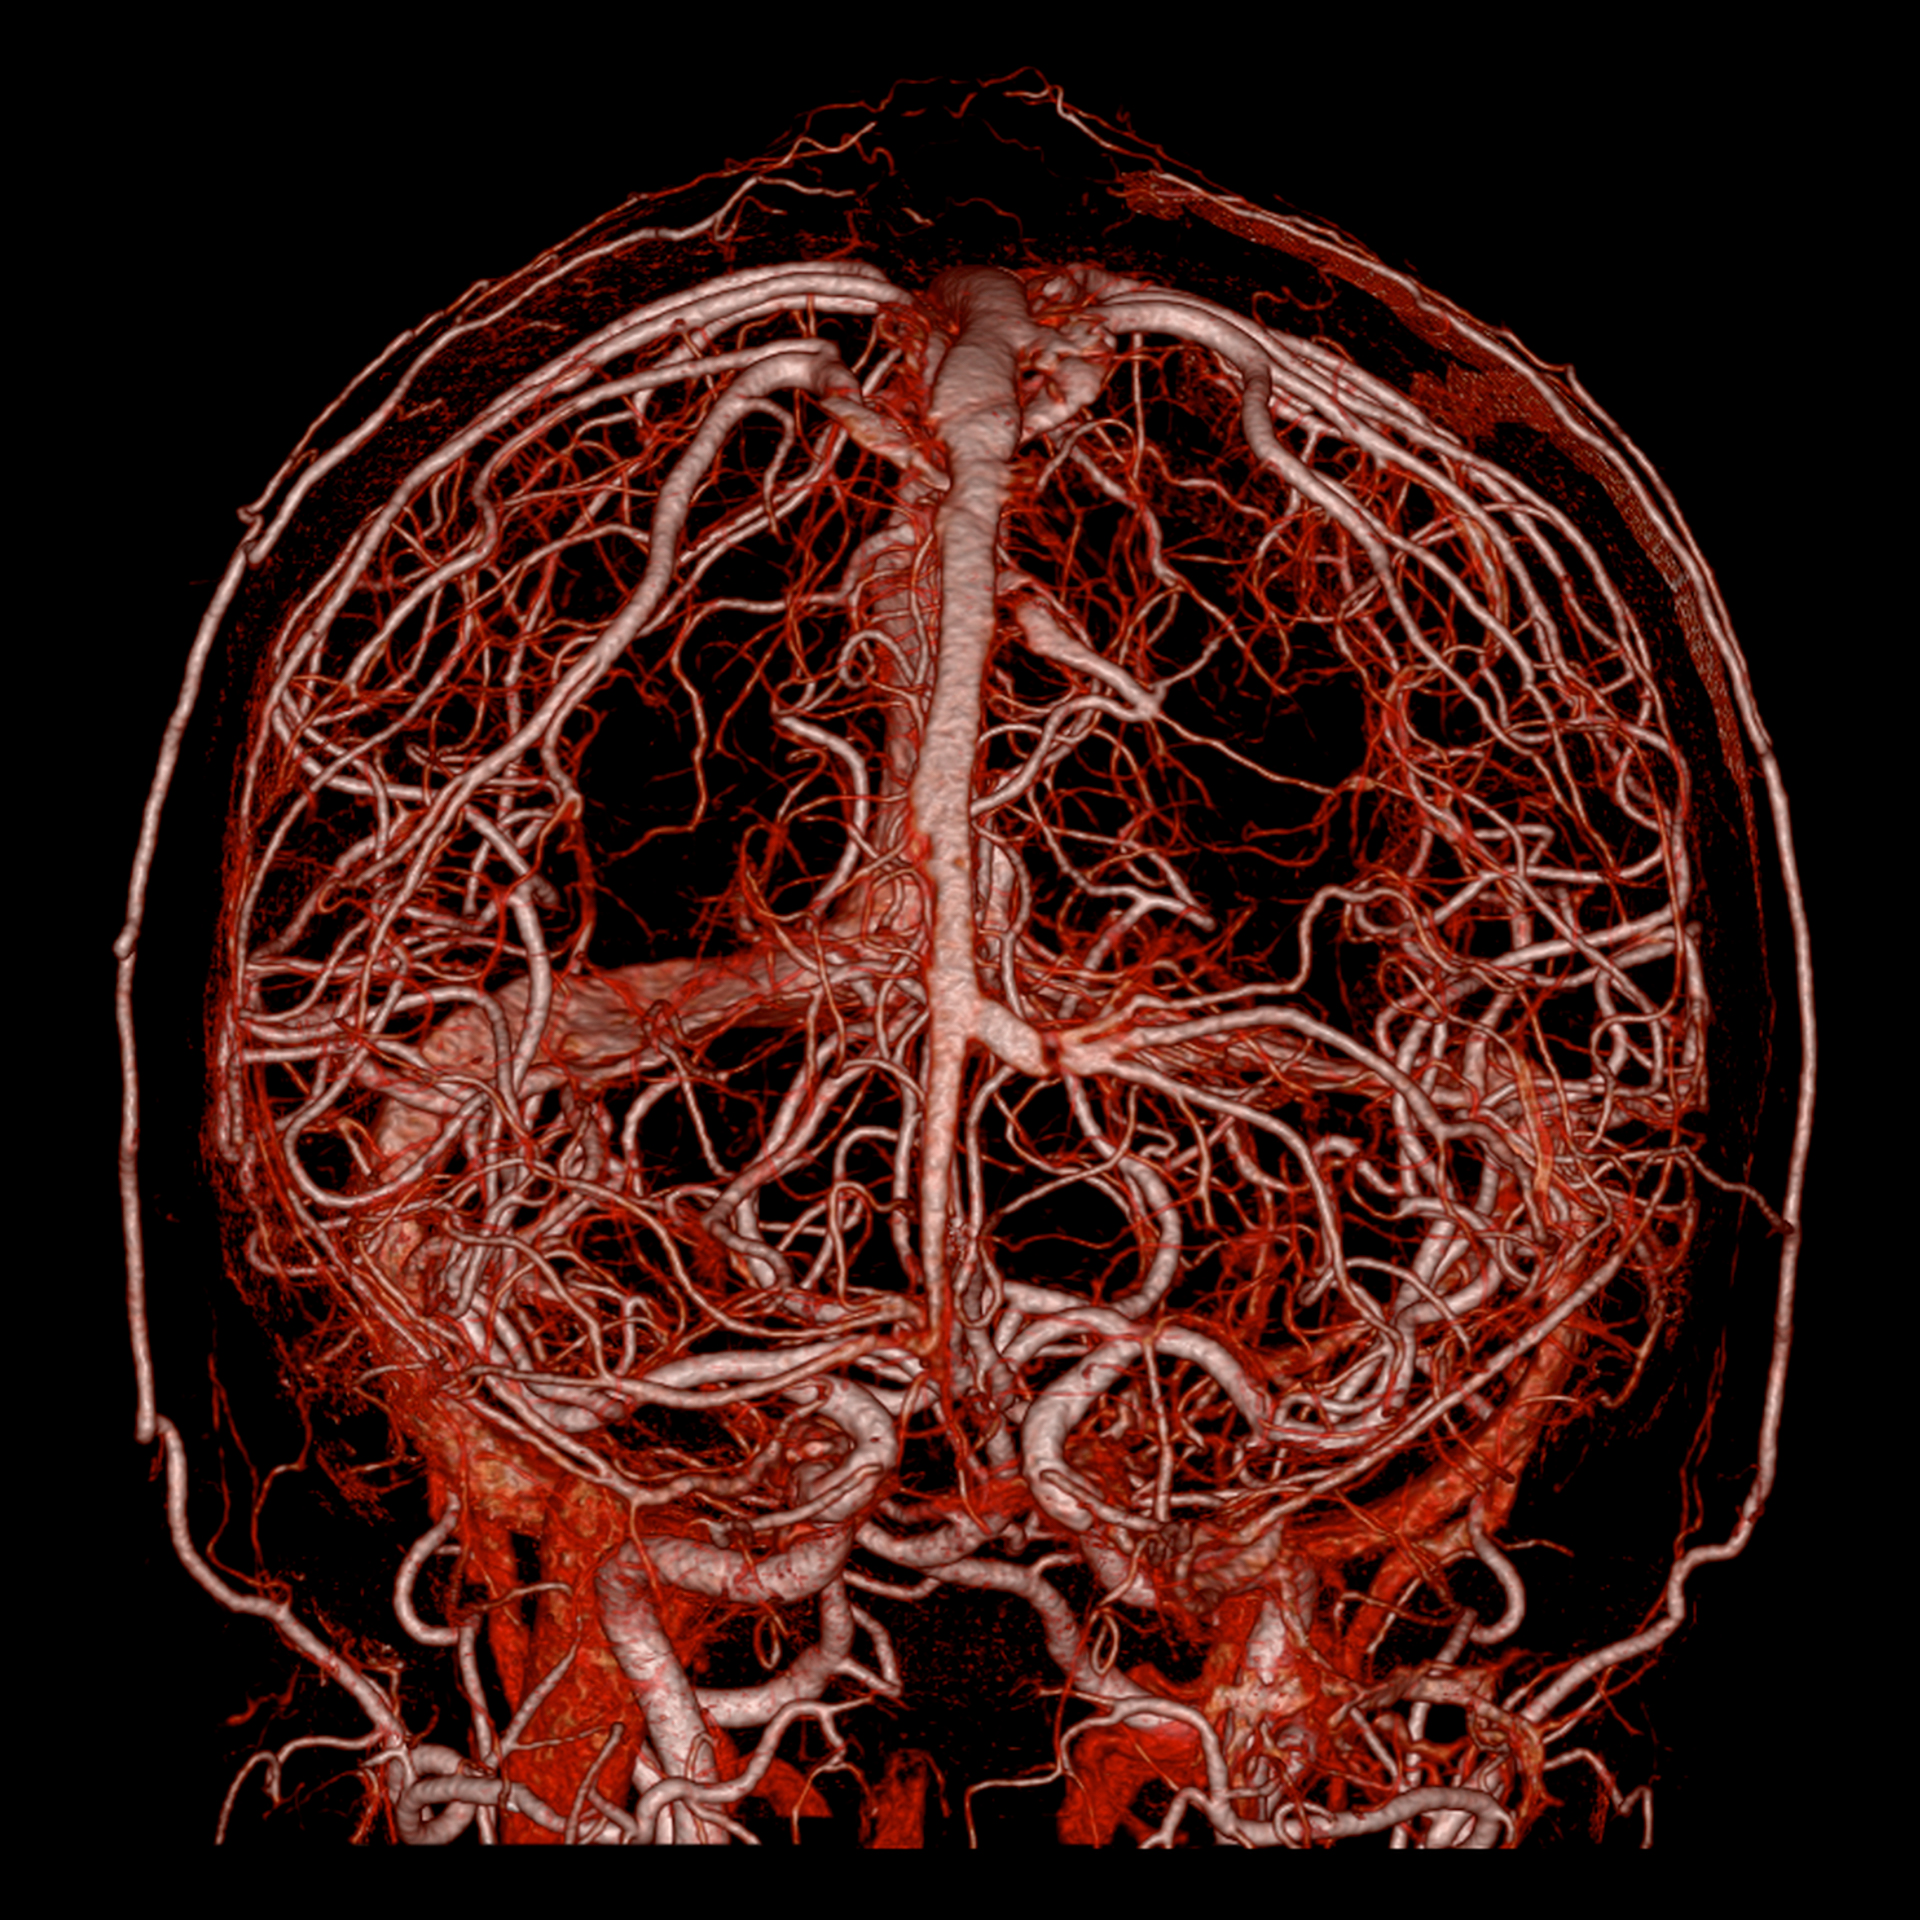

КТ ангіографія голови, 0,25 мм, 1024 матриця¹